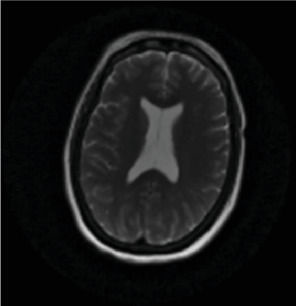

迟发性缺氧后白质脑病(DPHL)是一种罕见的诊断,可能与其他更常见的神经系统疾病(如紧张症)相似。虽然一氧化碳中毒很常见,但也可能是由于其他原因引起的缺氧,如药物过量或心脏骤停。由于其症状的迟发性和与其他疾病的重叠,最初可能被误诊。我们报告一名50岁女性患者,有抑郁史,在家中发现无反应、缺氧和发热,时间不详。最初担心的是败血症。最初的头部计算机断层扫描(CT)和脑部磁共振成像(MRI)正常。患者有横纹肌溶解伴继发性肾衰竭、肝休克和急性胰腺炎。药物稳定后,她的认知能力恢复到正常基线。然而,在住院10天后,她的精神状态恶化,表现为沉默、麻木、凝视、口服摄入量减少和毅力。怀疑继发于重度抑郁发作的紧张症。劳拉西泮向上滴定无结果。劳拉西泮无反应提示再次进行脑部MRI检查,显示双脑额叶、颞叶、顶叶和枕叶弥漫性白质改变。诊断为DPHL。随后,她开始服用卡比多巴/左旋多巴25/100 mg,情况有所改善,并出院至康复机构。

Delayed posthypoxic leukoencephalopathy (DPHL) is a rare diagnosis that may present similarly to other more common neurological conditions, such as catatonia. While often seen with carbon-monoxide poisoning, it can also be due to anoxia due to other causes, such as drug overdose or cardiac arrest. Due to the delayed nature of its symptoms and overlap with other conditions, it can be initially misdiagnosed. We present a 50-year-old female patient with a history of depression who was found unresponsive, hypoxic, and febrile at her home for an unknown amount of time. The initial concern was for sepsis. Initial computed tomography (CT) of the head and magnetic resonance imaging (MRI) of the brain were normal. The patient had rhabdomyolysis with secondary renal failure, shock liver, and acute pancreatitis. Once medically stabilized, her cognition returned to a normal baseline. However, 10 days into her hospitalization, her mental state deteriorated, displaying symptoms of mutism, stupor, staring, decreased oral intake, and perseveration. Catatonia, secondary to a major depressive episode, was suspected. Lorazepam was titrated upward without result. Lack of response to lorazepam prompted a repeat brain MRI, revealing diffuse white matter changes in the frontal, temporal, parietal, and occipital lobes of both hemispheres. A diagnosis of DPHL was made. She was then started on carbidopa/levodopa 25/100 mg with improvement and was discharged to a rehabilitation facility.